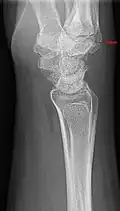

Carpometacarpal bossing (or metacarpal/carpal bossing) is a small, immovable mass of bone on the back of the wrist. The mass occurs in one of the joints between the carpus and metacarpus of the hand, called the carpometacarpal joints, where a small immovable protuberance[1] occurs when this joint becomes swollen or bossed.

The joint between the index metacarpal and the capitate is a fibrous non-mobile joint. Some people have a gene that leads to this growth. It looks like arthritis (bone spurs on each side of the joint) on X-ray. It looks like a ganglion on the hand, but more towards the fingertips.

The carpometacarpal joint is usually found at the base of the second and third metacarpal bones at the point where they meet the small bones of the wrist.[2]